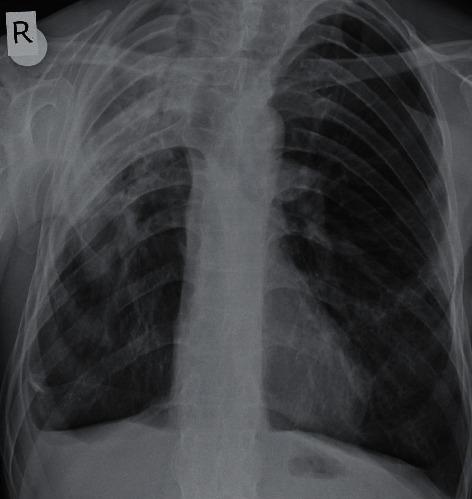

Pulmonary apical fibrosis is a rare complication of ankylosing spondylitis (AS). The essential characteristics of this lesion are its very slow progression and frequently asymptomatic nature. Herein, we are presenting a patient with AS who rapidly developed pulmonary apical fibrosis in a 3-year period despite decreased musculoskeletal pains. The 60-year-old male applied with complaints of progressively increasing cough in the recent two years, dyspnea, and fatigue. He had no chronic disease except AS. He had no continuous medication except nonsteroid anti-inflammatory drugs for 2-3 days monthly since his musculoskeletal pains decreased in the recent years. His physical examination revealed reduced breath sounds in the upper zones of the right lung. Chest X-ray revealed increased diffuse opacity in the upper zones of the right lung. Thoracic high-resolution computed tomography showed a consolidation accompanied with traction bronchiectases compatible with chronic fibrosis in the upper lobe of the right lung. However, thoracic computed tomography of the patient performed 3 years ago did not reveal pulmonary apical fibrosis and parenchymal destruction. Biopsy revealed no finding of malignancy, granulomatous inflammation, or vasculitis. The results of cultures were negative. So, the patient was diagnosed as pulmonary involvement of AS, which developed in a 3-year period. This case has shown that extra-articular complications may continue to develop in patients with AS even if their musculoskeletal complaints have subsided. So, patients with AS should be followed up regularly with systemic examinations.

肺尖纤维化是强直性脊柱炎(AS)的一种罕见并发症。该病变的基本特征是进展非常缓慢且通常无症状。在此,我们报告一名AS患者,尽管其肌肉骨骼疼痛减轻,但在3年内迅速发展为肺尖纤维化。这位60岁男性因近两年来咳嗽逐渐加重、呼吸困难和疲劳前来就诊。除AS外,他无其他慢性疾病。由于近年来肌肉骨骼疼痛减轻,他除了每月服用2 - 3天的非甾体抗炎药外,没有持续用药。体格检查发现右肺上叶呼吸音减弱。胸部X线显示右肺上叶弥漫性模糊影增加。胸部高分辨率计算机断层扫描显示右肺上叶有实变,并伴有与慢性纤维化相符的牵拉性支气管扩张。然而,该患者3年前的胸部计算机断层扫描未显示肺尖纤维化和实质破坏。活检未发现恶性肿瘤、肉芽肿性炎症或血管炎。培养结果为阴性。因此,该患者被诊断为3年内发生的AS肺部受累。该病例表明,即使AS患者的肌肉骨骼症状已缓解,其关节外并发症仍可能继续发展。所以,AS患者应定期进行全身检查随访。